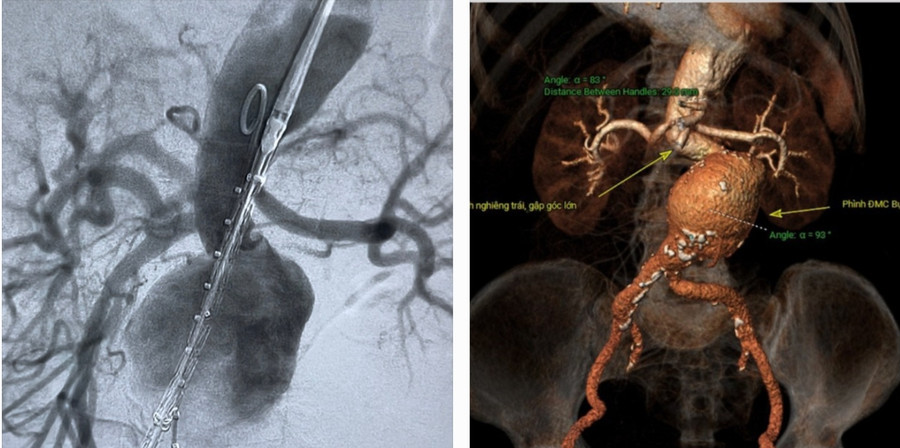

Qua thăm khám và xử trí cấp cứu ban đầu, các bác sĩ chẩn đoán bệnh nhân bị sốc do túi phình lớn động mạch chủ bụng dọa vỡ, nguy cơ vỡ cao. Sau đó, bệnh nhân được siêu âm bụng và chụp CT xác định túi phình rất lớn động mạch chủ bụng dọa vỡ.

![]() |

| Hình ảnh túi phình lớn động mạch chủ bụng nguy cơ vỡ rất cao trước can thiệp. |